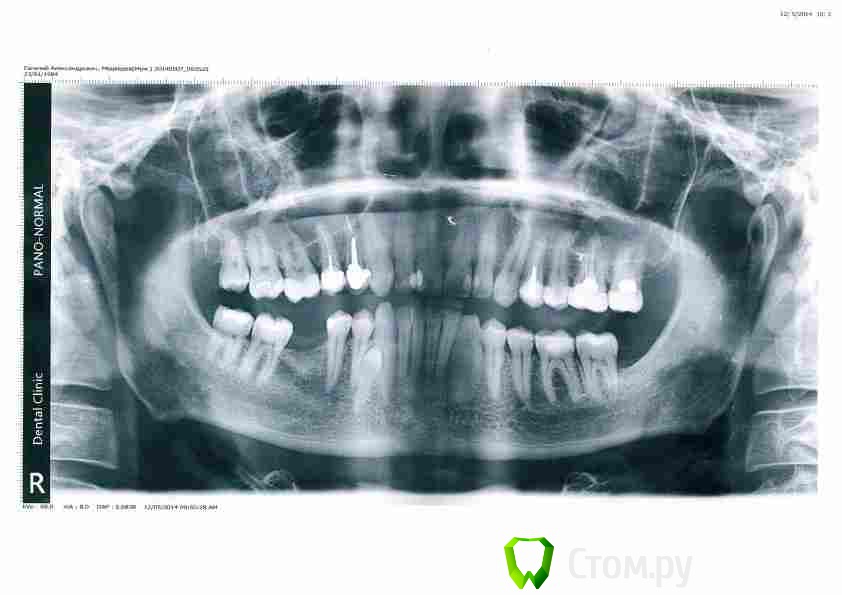

Medvedeve Опубликовано 28 августа, 2014 Поделиться Опубликовано 28 августа, 2014 (изменено) Добрый день! Я в 2010 г. удалял кисту верхнечелюстной пазухи, но спустя время опять образовалась. Консультировался с ЛОР-врачом в СПб, сказала что киста одонтогенная и необходимо разбираться с зубами. Обращался к стоматологам - разводят руками и к ЛОРу направляют обратно. Возможно Вы что-то посоветуете? В приложении направляю 1) Выписной эпикриз 2010г. после операции по удалению кисты 2) недавнее заключение по КТ 3) Ортоснимок свежий. зубы 4-ка и 5-ка под коронкой, корни уходят в верхнечелюстную пазуху. 5-ку делал еще операции 2010 года (пломбировка каналов и коронка), 4-ку не так давно. Мои подозрения на 5-ку... Скажите, если просто удалить причинный зуб может ли киста "самоликвидироваться" либо надо совмещать операции удаление зуба+удаление кисты? Основные жалобы на данный момент: напряжение и тяжесть за правой щекой, при вставании из положения лежа - болезненные ощущения в том районе (в корнях зубов), видимо гайморит еще появился. Сники КТ с программой icatvision выложил на яндекс-диск https://yadi.sk/d/BYmt_KHTaZFAZ Заранее благодарю за помощь, Евгений.эпикриз+заключение КТ.pdf Изменено 28 августа, 2014 пользователем Medvedeve Ссылка на комментарий

Bier Опубликовано 30 августа, 2014 Поделиться Опубликовано 30 августа, 2014 По орто есть ощущения, что каналы зубов запломбированы неудовлетворительно, а 16з уже невитальный. Я не крутил КТ (качать его долго). Если это так, то удалять зубы не нужно, но перелечить каналы надо. Потом наблюдать. Ссылка на комментарий